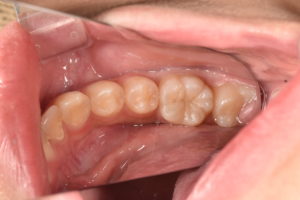

所見:左下第一大臼歯に歯髄に近接した大きなう蝕をみとめる。自発痛などの症状はない。う蝕を除去する際に歯髄が露出する可能性が高い。

通常の治療では根管治療により歯髄を除去することが考えられる状況であるが、臨床症状がなく、年齢も若い子とから歯髄温存療法を行うこととした。